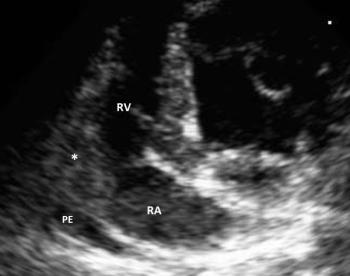

Considerations for the use of echocardiography to evaluate suspected tumors located in the heart.